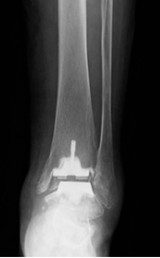

人工足関節置換術

術前レントゲン写真

術後レントゲン写真